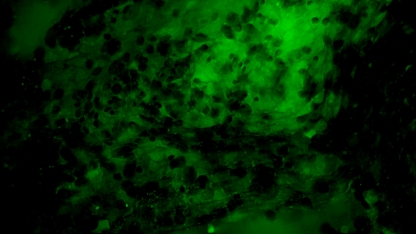

术中EndoSCell®细胞图像如下:

1.可疑组织的肿瘤细胞残留:细胞核异型性显著,分布密集且不规则。